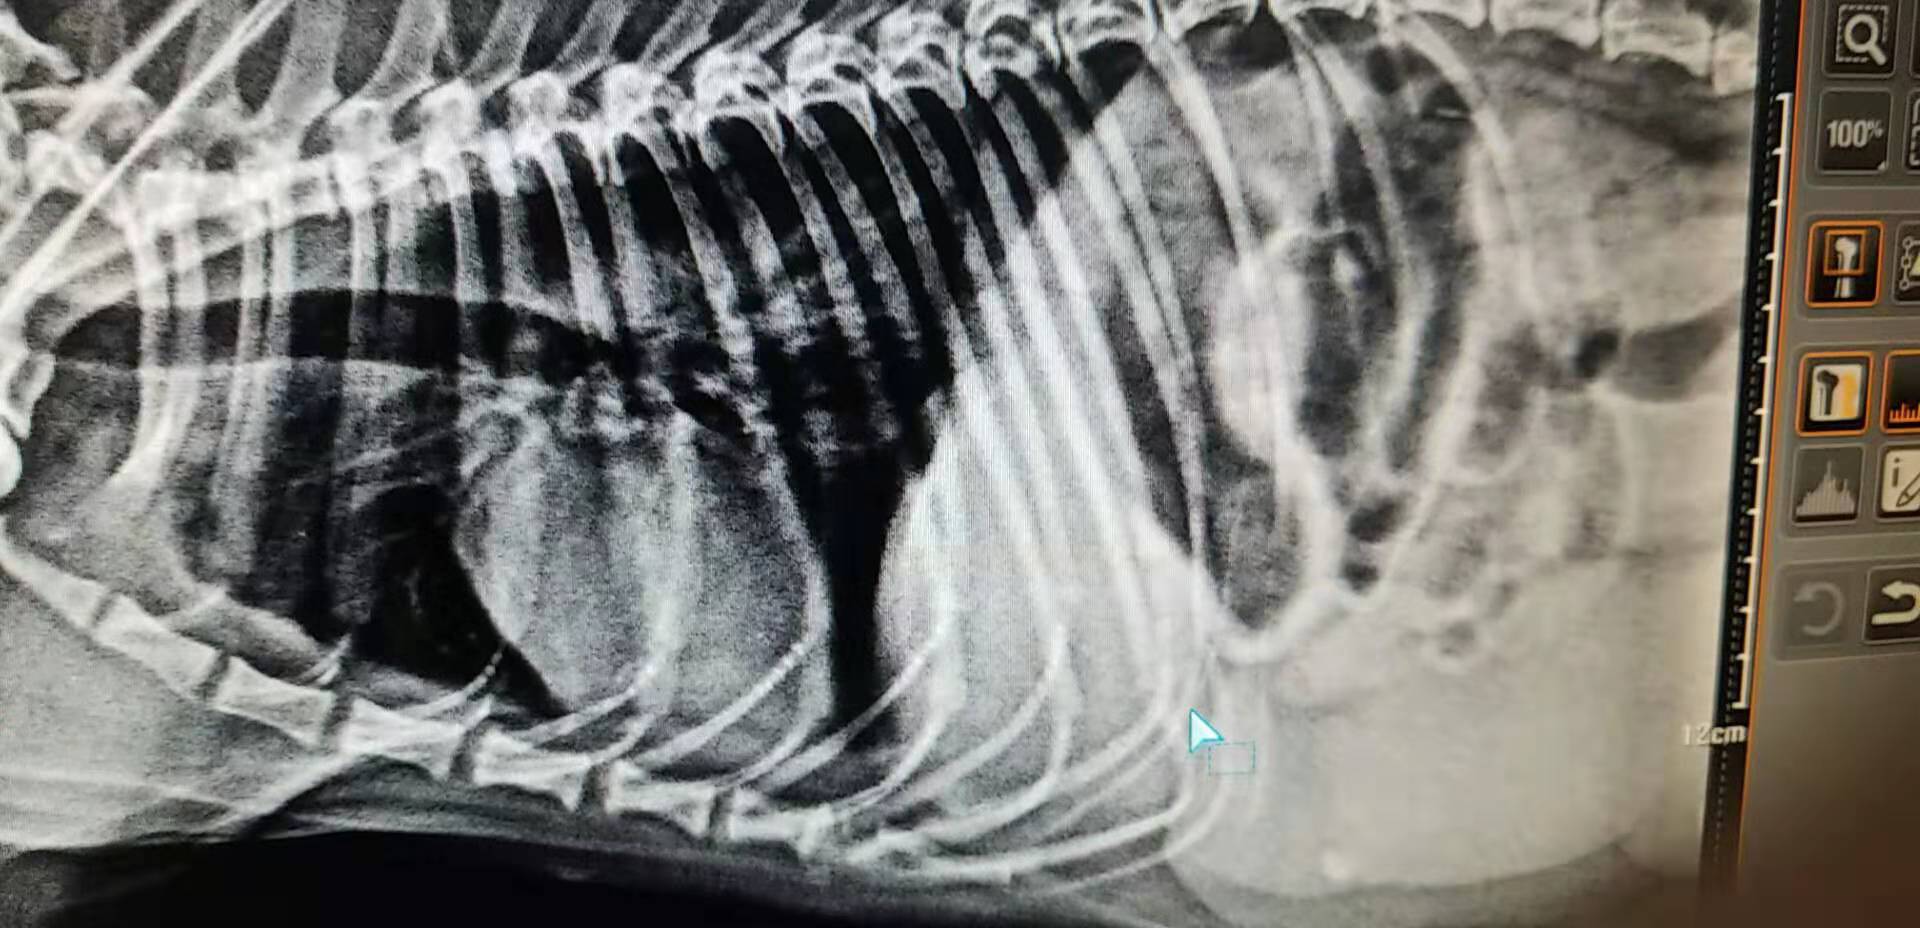

X光的摄片

- 实验室检查:血常规白细胞指标升高约4倍,生化球蛋白升高,x光可见腹腔子宫位置扩张占位。B超下腹腔多个液性暗区,最大子宫直径可达5cm。

- x光的检查:可见腹部子宫区有强回声占位。